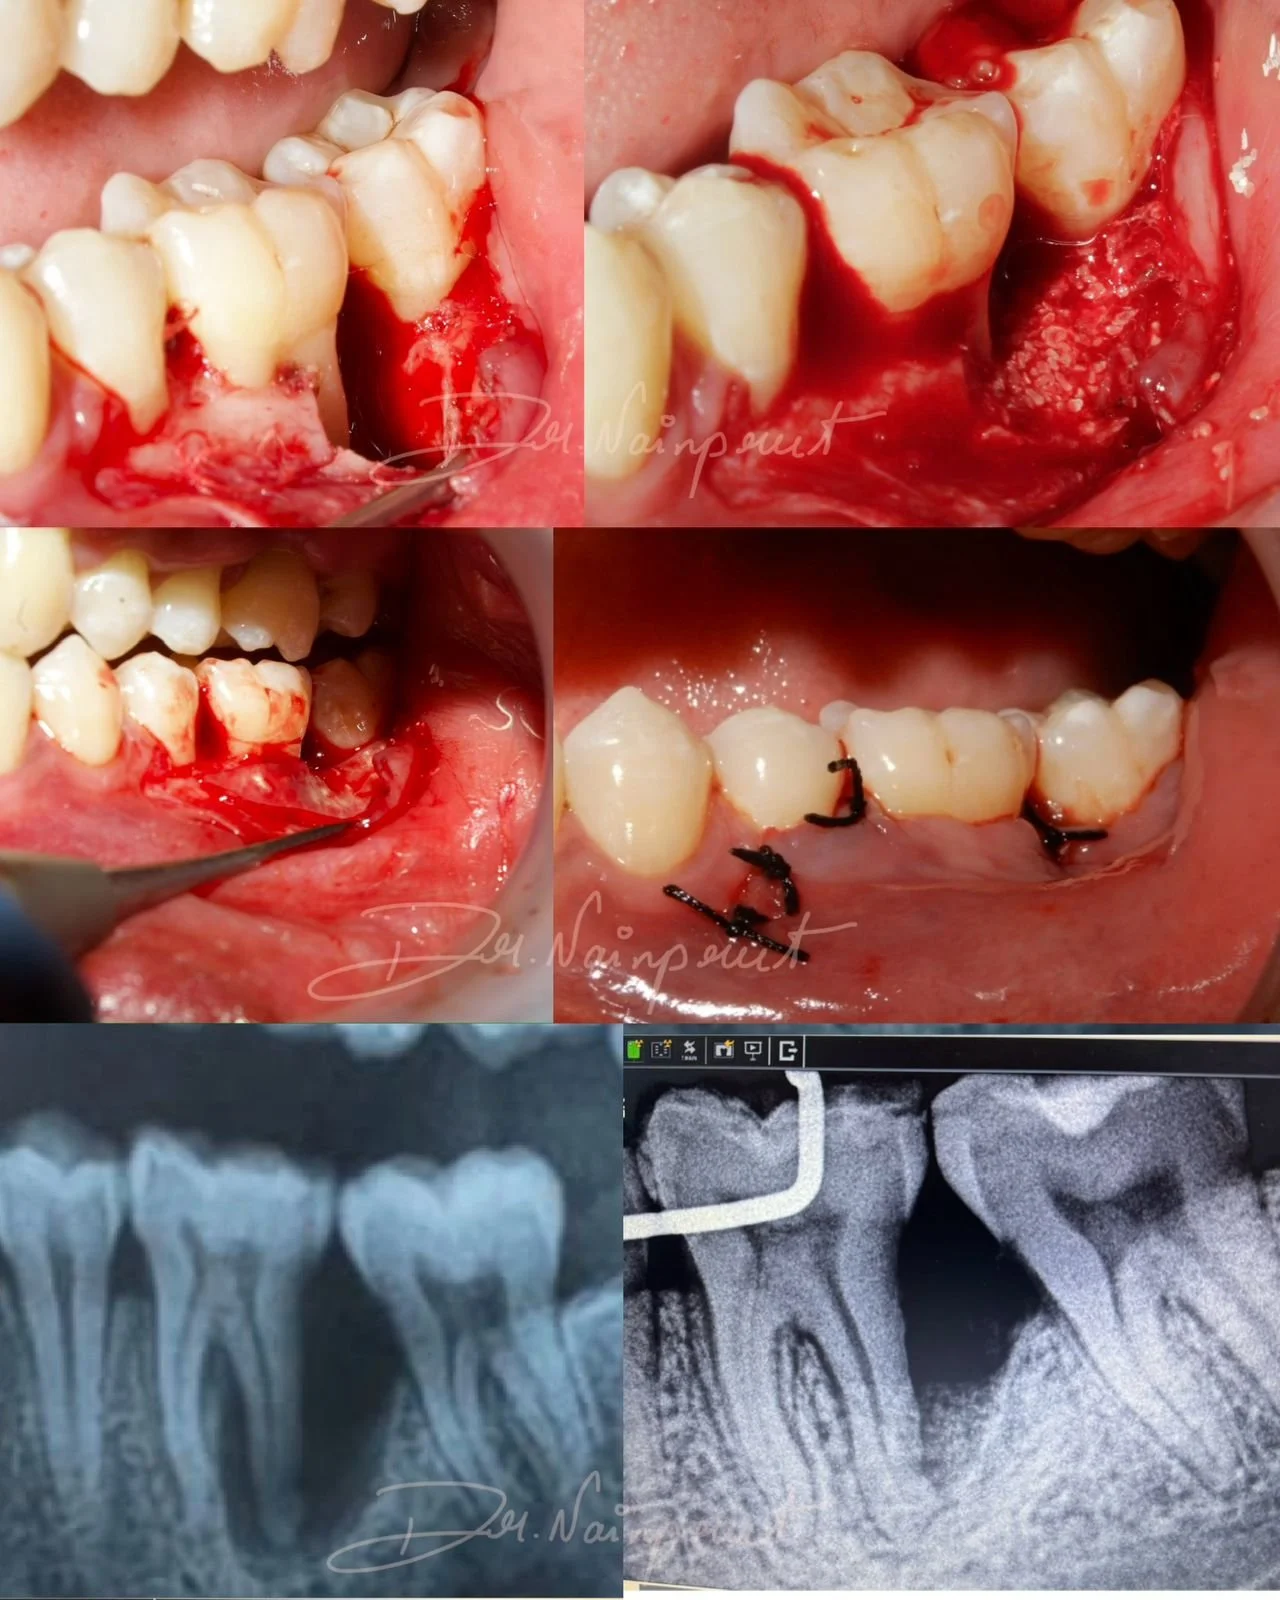

Management of Endo perio lesion with regenerative surgery

Case done by Dr Nivedha, III year post graduate student